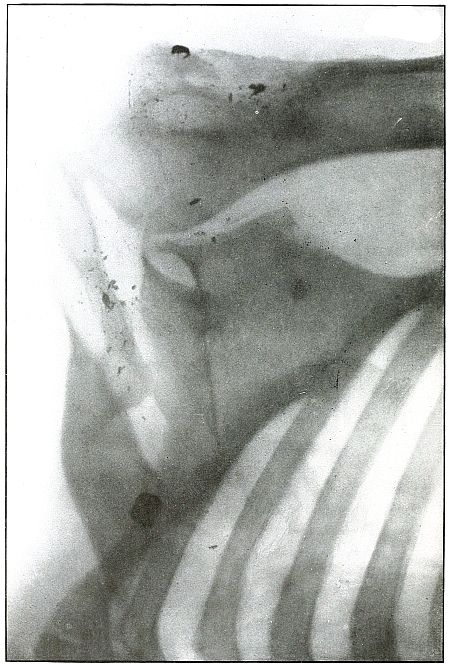

Rifle—Plate 2.

HEAD.

Gunshot Wound of the Head, with Lodgment of the Missile.

Wound of entrance, near outer canthus, with course through eyeball to

ethmoid body.

Wound of exit, none.

The Bulgarian Mannlicher bullet, shown half actual size on the plate,

must be inclined on its long axis, about 30° from the perpendicular,

to the plane of the plate.

The slight penetration of the missile and its normal character show

that, having struck no intervening object, it indicted the wound at

extreme range.

The treatment should meet the indication for removal of missiles in

all superficial or easily accessible locations and when they cause

reaction.

Results to be expected are favorable except for loss of the eye.